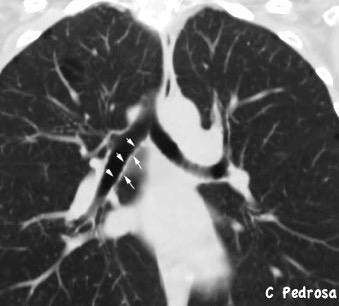

40. BRONQUIO LSD. ANATOMÍA

41. BRONQUIO LSD. PATOLOGÍA

42. BRONQUIO LSI. ANATOMÍA

43. BRONQUIO LSI. PATOLOGÍA